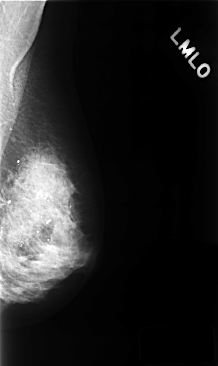

C_0394_1.LEFT_MLO

LEFT_MLO LINES 4752 PIXELS_PER_LINE 2832 BITS_PER_PIXEL 12 RESOLUTION 50 NON_OVERLAY